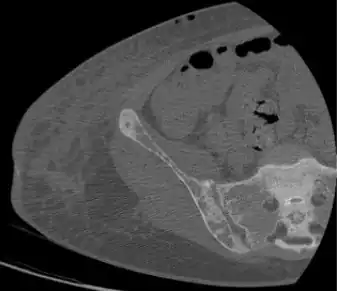

Brown tumors in the pelvis and a hip fracture.[17] -